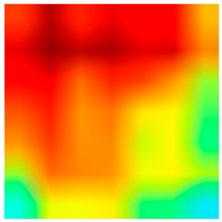

2.4. Model Interpretability

3.6. Visualizing Interpretability in CRC Classification Using ADFMs

| Grade-CAM | Gradient-Weighted Class Activation Mapping |